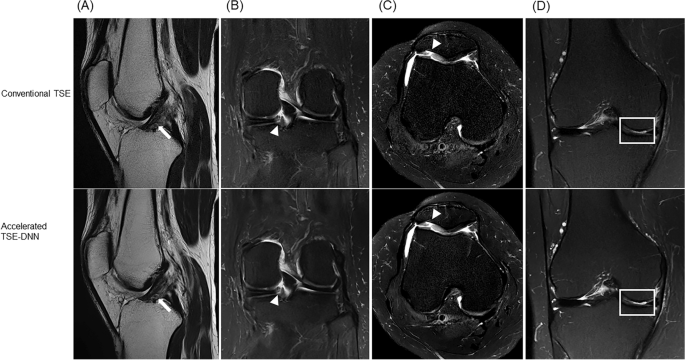

Representative images for comparable image quality are shown in Fig. 4. The accelerated image exhibited fewer motion-related artifacts, while the TSE-DNN image displayed improved image quality. However, certain artifacts from parallel imaging persisted in the TSE-DNN image, as depicted in Fig. 5.

Conventional and reconstructed images of accelerated sequences: a 64-year-old woman with knee pain (A–D). Motion-related artifacts in conventional FSE (A upper, arrow) is not seen on accelerated image (A middle), and the image is enhanced on FSE-DNN image (A lower). Overall image quality is comparable in both conventional FSE and FSE-DNN images (B and D). However, parallel imaging artifacts cannot be completely removed in FSE-DNN image (C middle and lower, arrowheads). The first row represents conventional FSE images, the second row represents accelerated FSE sequences, and the third row represents DNN-reconstructed images of FSE-DNN. Each column represents the images reconstructed by axial fat-saturated T2-weighted image, sagittal T2-weighted image, coronal fat-saturated T2-weighted image, and axial T1-weighted image.